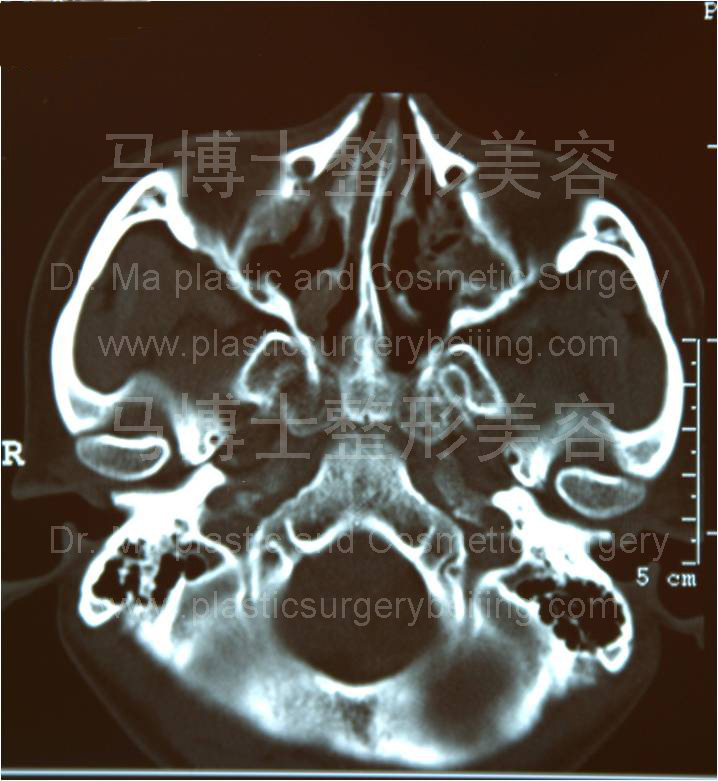

同一受术者术前术后CT断层,断面为经过颧弓的水平断面。左侧术前CT片可见颧弓弓度较大,右侧术后者弓度较小,颧弓变直。这种变化使两侧颧弓最突出点的距离变小。面部宽度变窄。